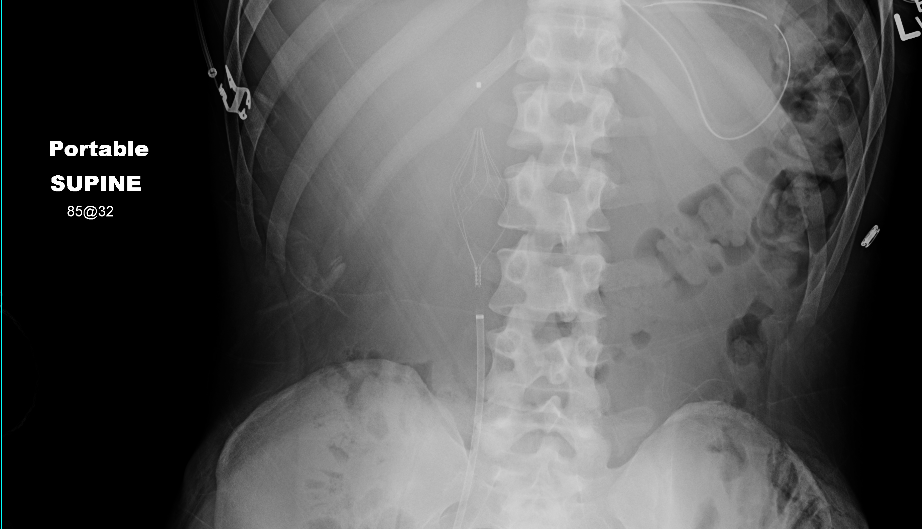

The Angel® Catheter allows for bedside placement with no need to move the patient to an endovascular suite. Following placement of the Angel® Catheter, proper positioning of the filter can be confirmed via an abdominal radiograph (KUB). After the KUB the filter can be repositioned as needed.